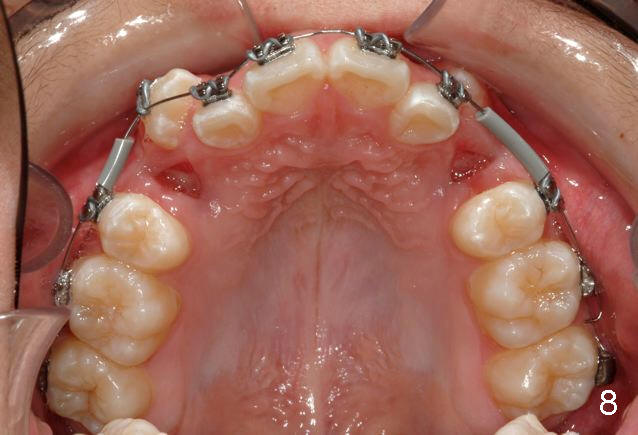

Great job removing the teeth, especially #22.  I placed the braces on the upper teeth on Tuesday.  Toby had a terrible cough (poor guy) and it was quite challenging as a result.  Just imagine seeking that perfect bracket placement in between coughs!!!  So, we will place the lowers another day and permit more healing of the #22 site.  I hope you guys had a nice Thanksgiving.  Have a great weekend.  Tim

P.S. I do not take the first small gauge NiTi AW back to the 7s at appointment #1, to A) make sure of a good 7 bond (as they are most difficult to isolate), B) to prevent a wire poke if a 7 should come off, and C) minimize the chance of a very flexible AW pulling out of the 7.  If the 7s are still bonded at appointment #2, I trust I have a good bond and then include the 7 with every subsequent AW change.  I thought I would share that little tip with you:-)

Tim: Thank you so much for the tip.  It appears that an alastik is placed between #6 bracket and the upper AW.  Can you recommend surgical exposure of #11?

We are teasing tooth #6 down initially with a light elastic force. This will minimize any reciprocal forces on the anterior teeth. I do not want to intrude the incisors while extruding 6. That would potentially open the bite.

You will see tooth #11 continue to erupt spontaneously. In the initial photos, it was not visible. It was simply mechanically blocked out. And the tissue will b the best when the tooth erupts spontaneously. Bet on 11 to erupt😉 and a couple more mm of eruption and I will b able to place a button and like 6, begin to tease down faster.